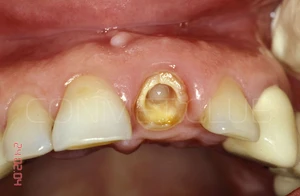

Вид на лунку удаленного зуба. Щипцы при удалении не использовались, только кюретажная ложка СМ 2/4 и прямой элеватор.

Сразу после экстракции зуба 21 производится установка имплантата КОНМЕТ с полированной трансгингивальной частью высотой более 3 мм. Интерфейс имплантата - просто конус Морзе и ни каких антиротационных шестигранников!